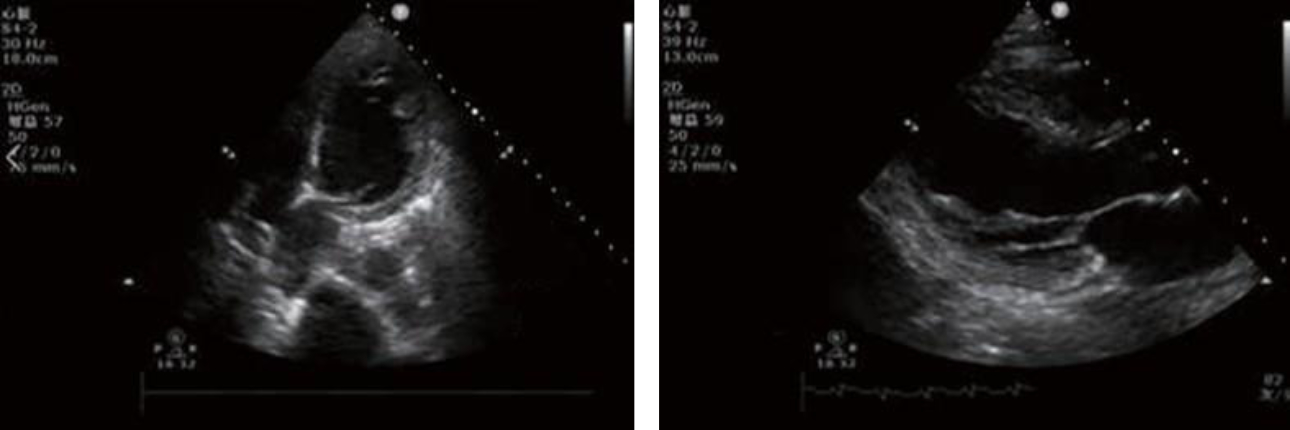

Echocardiography:

Heart function parameters: LVDd: 48 mm

LVEF: 20%M-mode

2-DE: normal dimension of atrium-ventricle, no enlargement of the ascending aorta, an obvious primary wave, a clear dicroitic wave, and a clearly visible aortic valve that opened and closed normally; a slender mitral valve composed of an anterior leaflet with two waves, and a posterior leaflet moving in the opposite direction to the anterior leaflet.

Ventricular wall thickening is absent, and movement of the ventricular septum and the posterior wall of the left ventricle is in opposite directions.

Obvious attenuation of beats of the middle segment and apex of the left ventricle at rest, and fair motility of its base.

DOPPLER: Color Doppler ultrasound showed signals of small amounts of regurgitation through the mitral and tricuspid valves.

Figure 1

Diagnostic comments: Decreased left ventricular systolic function (LVEF: 20%), Takotsubo syndrome (stress cardiomyopathy) to be excluded, and mild mitral and tricuspid regurgitation.